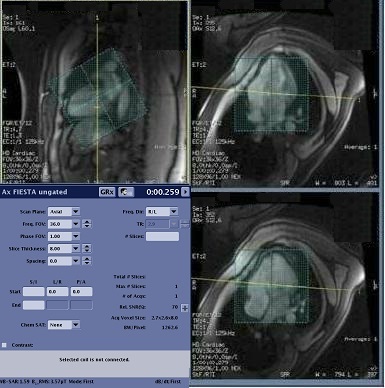

3. Place a small FOV shim volume over the heart.

• The shim volume FOV should be approximately half the size of the scan FOV. For example, if the scan FOV is 36 cm, then the shim volume FOV should be 18 cm. For more details, see Shim volume procedure.

Figure 1. Shim volume over heart